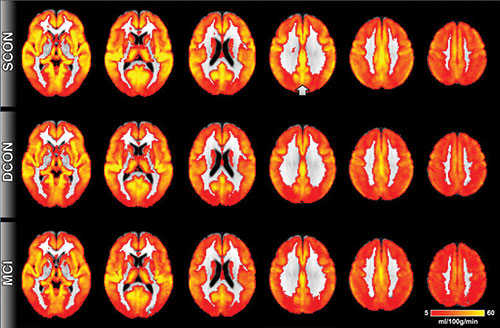

Perfusione cerebrale. Il rosso indica una bassa perfusione, il giallo indica alta perfusione. Nel complesso, la perfusione cerebrale è simile nei 3 gruppi. La differenza più importante è presente nella corteccia cingolata posteriore (indicata dalla freccia), un'area vicina alla linea mediana nella parte superiore e posteriore del cervello. I partecipanti di controllo che rimangono stabili hanno una maggiore perfusione rispetto ai deteriorati e agli MCI.Una tecnica di risonanza magnetica (RM) può rilevare i segni di declino cognitivo nel cervello ancor prima della comparsa dei sintomi, secondo un nuovo studio pubblicato online sulla rivista Radiology.

Dei 148 individui sani, 75 sono rimasti stabili, mentre 73 erano deteriorati cognitivamente dopo 18 mesi di controllo clinico. Quelli deteriorati avevano mostrato una ridotta perfusione all'esame basale di risonanza magnetica ASL, in particolare nella corteccia cingolata posteriore, una zona al centro del cervello che è associata con la rete di modalità predefinita, la rete neurale che si attiva quando il cervello non è concentrato su un compito specifico. Il declino in questa rete è visibile nei pazienti con MCI ed è più pronunciato nei pazienti con Alzheimer.

Il modello di perfusione ridotta nel cervello degli individui sani che hanno in seguito sviluppato deficit cognitivo era simile a quello dei pazienti con MCI. "C'è uno stretto legame che conosciamo tra l'attività neurale e la perfusione cerebrale nella corteccia cingolata posteriore", ha detto il dottor Haller. "Una minore perfusione indica un'attività neurale diminuita". I risultati suggeriscono che gli individui con perfusione diminuita rilevata con la RM-ASL possono mantenere temporaneamente il loro stato cognitivo attraverso la mobilitazione della loro riserva cognitiva, ma finiranno per sviluppare deficit cognitivi sottili.